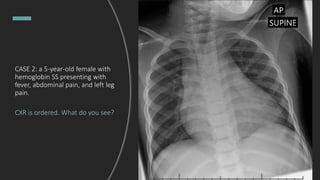

CASE 2: a 5-year-old female with

hemoglobin SS presenting with

fever, abdominal pain, and left leg

pain.

CXR is ordered. What do you see?

CASE 2: a 5-year-old female

with hemoglobin SS presenting

with fever, abdominal pain, and

left leg pain.

What do you see?

- Enlarged cardiomediastinal

silhouette consistent with diagnosis

of sickle hemoglobinopathy

- No focal consolidations

- Normal rib expansion

What about the lateral film?

CASE 2: 5-year-old

female with hemoglobin SS

presenting with fever, abdominal

pain, and left leg pain

Impression: Opacity at posterior lung

bases.

Tip: On lateral film you should be able to

see sharp costal vertebral angles (yellow

lines). On this film you have blunting of

those angles (arrows).

Final Dx: Acute Chest Syndrome